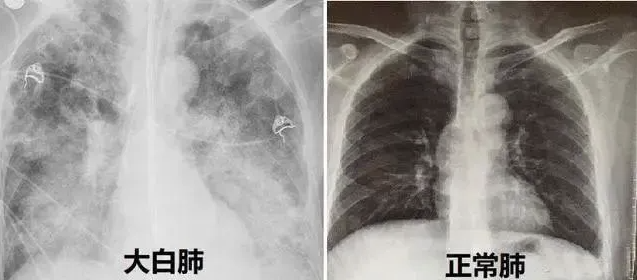

汉氏联合集团上饶经开汉氏联合医院:干细胞治疗白肺安全、有效